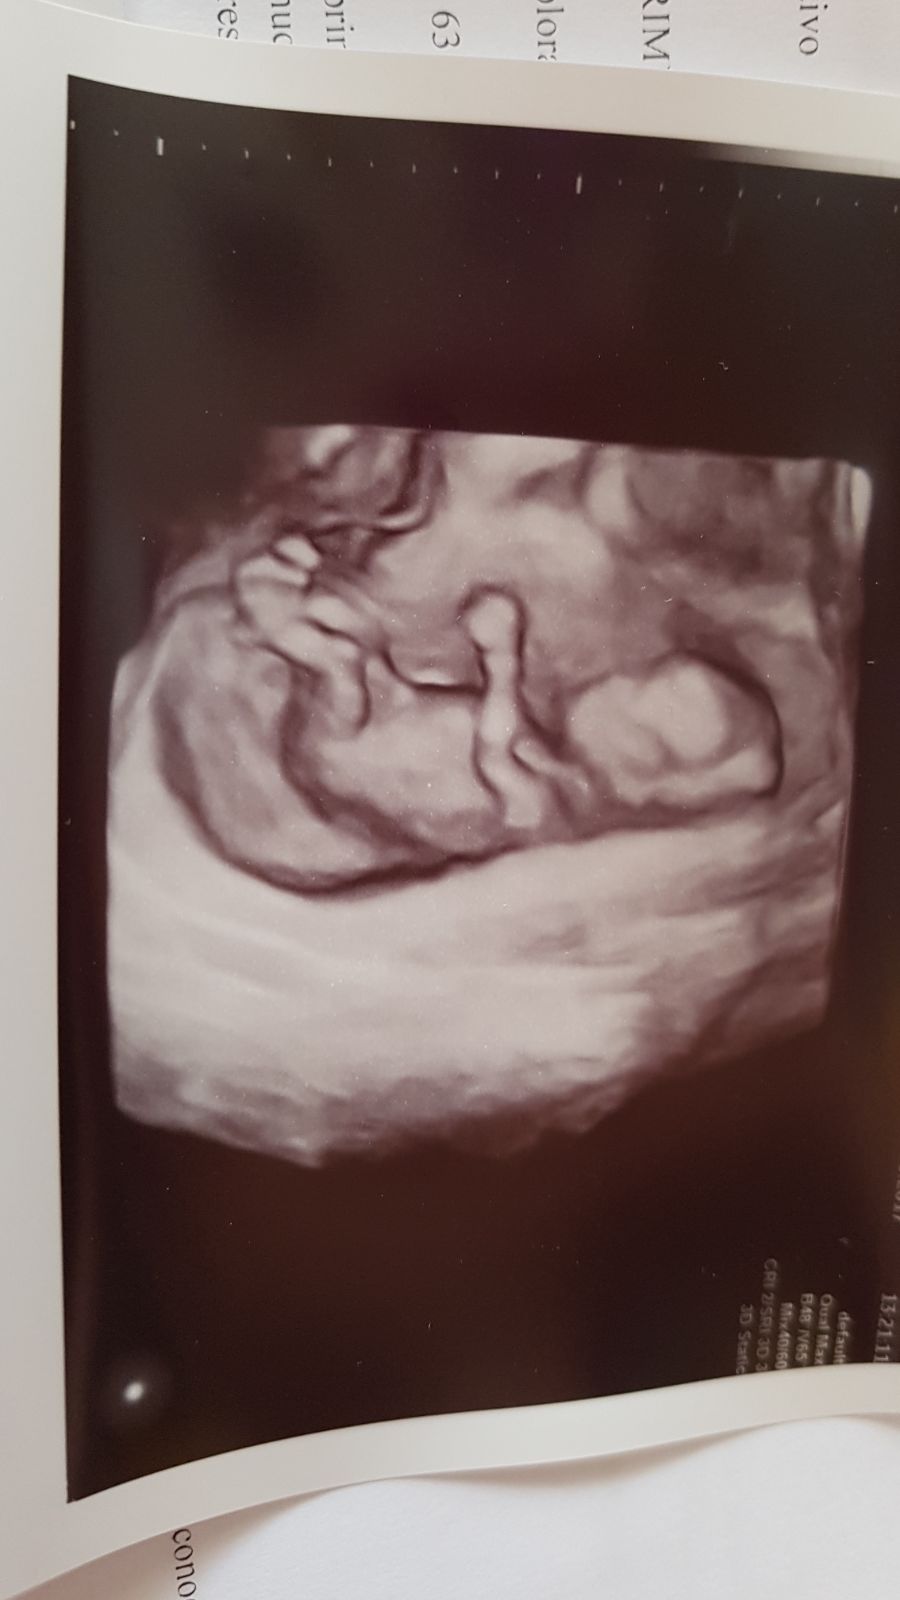

Cześć. Ja też jestem w Gyncentrum tylko wizyty mam w oddziale w Bielsku. Prowadzi mnie dr Piekarz-bardzo sympatyczna kobieta, wszystko dokładnie tłumaczy. Korzystam z programu 2+1. Trzecia procedura wtedy jest gratis. W cenie są wizyty, badanie hormonów w czasie stymulacji, punkcja+rozwój zarodków, 1 transfer, beta. Płacisz dodatkowo za badania, leki, mrozenie (zarodków i oocytów), kriotransfery.